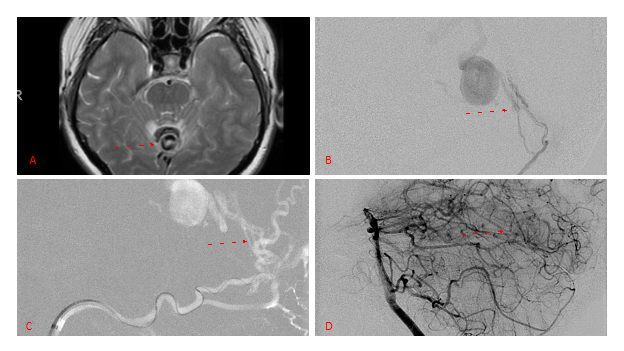

Figure 3. Right ECA AP and Lateral angiograms Pre (A and B) and Post NBCA embolization (C and D) Demonstrate near complete obliteration of right Occipital and Middle Meningeal Artery Fistulas